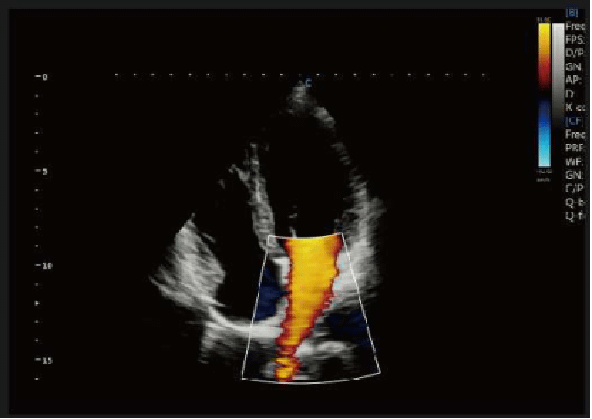

• B, 2B, 4B, B/M, B/BC, CFM, PW, Power Doppler/Directional PD, Instant Triplex, Duplex, Quadplex, Trapezoidal, Chroma B&M&PW, Full Screen

Phần mềm siêu âm chuyên tim: ECG Software,CW, TDI, HPRF,Free Steering M, Color M

Intelligent Doppler

• Tự động điều chỉnh hướng ROI, PFR ở chế độ màu, cổng doppler ở chế độ PW

• Hiệu quả hơn, dễ dàng thực hiện đo lường

• Cho phép tập trung vào bệnh nhân tốt hơn